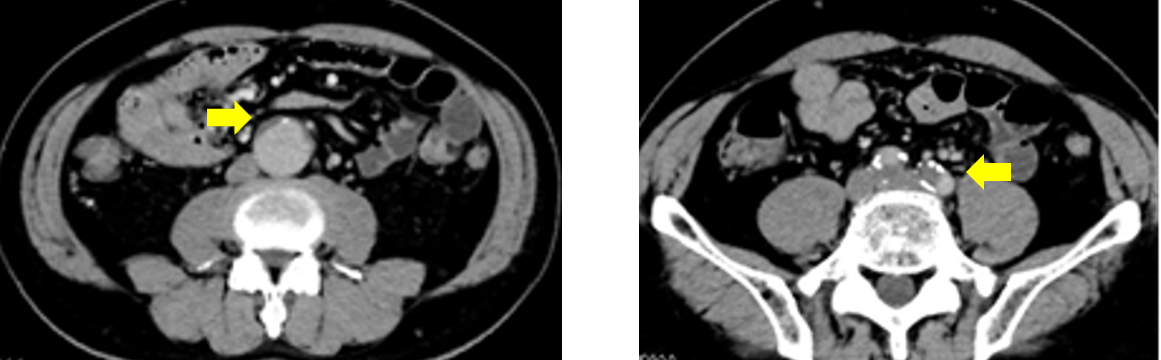

冠動脈CTA撮影後のDelayでのAorta撮影の画像を下記に提示します。通常の120kVpで撮影された画像と比較して、TEDLの画像の方が造影コントラストが得られますので、当院では、全例でTEDLを活用しています。

実際に、冠動脈CTA施行時にAAAとCIAに壁在血栓のある症例ですがdelay撮影でも十分な存在確認ができています。

Ascend_ayase13.png

TEDLを活用した血栓評価